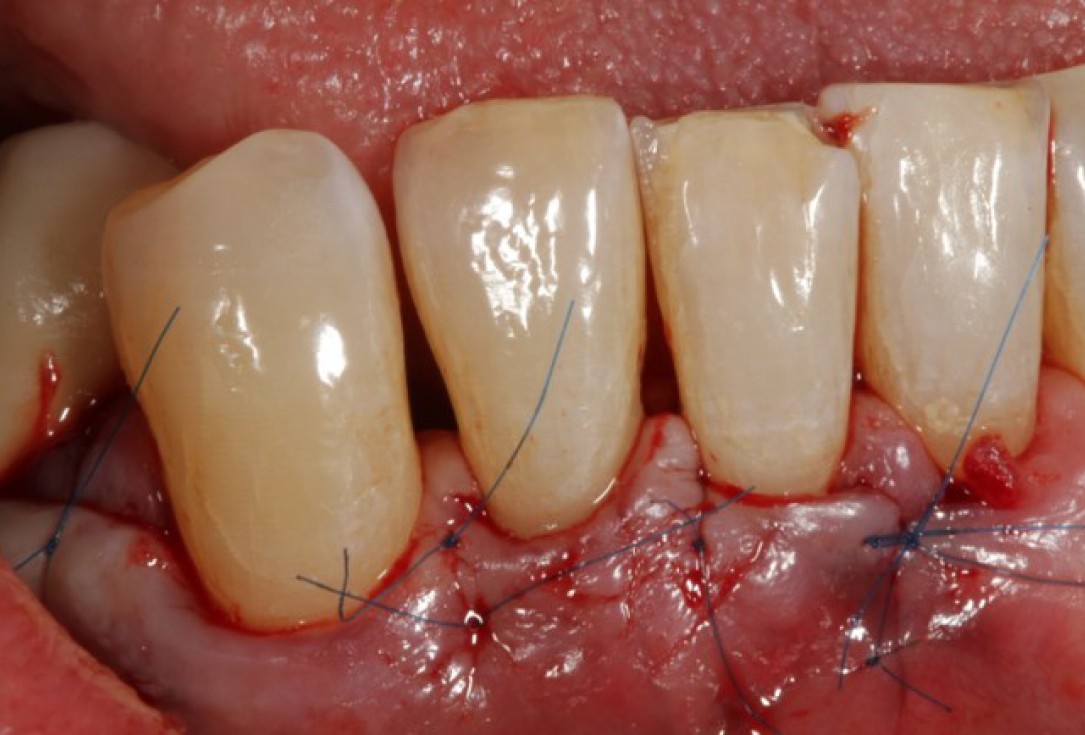

07/08 - Flap repositioning and suturing.

Non-contained intrabony defect treated using Straumann® Emdogain® and a synthetic bone grafting material - Prof. Dr. Dr. A. Kasaj